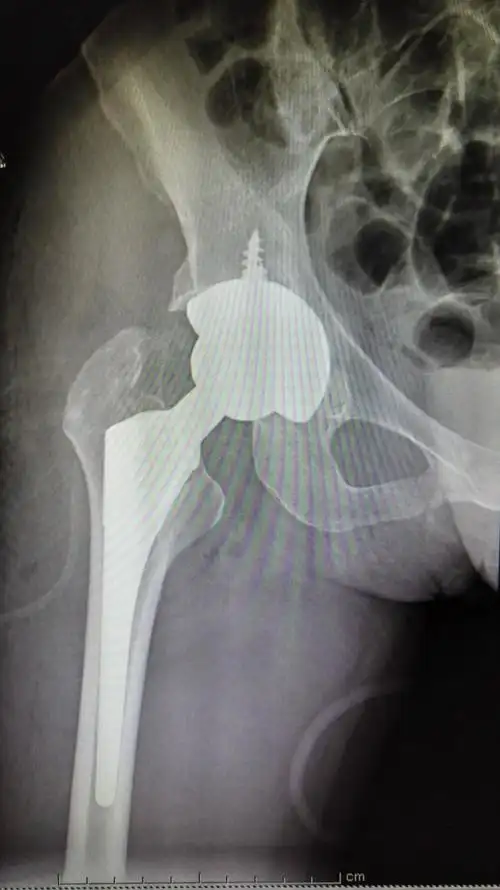

髋关节后脱位伴髋臼后壁骨折

髋臼后壁骨折并股骨头脱位